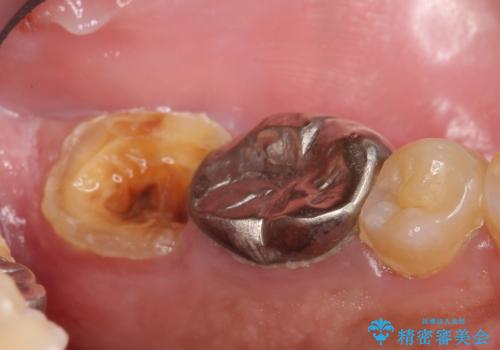

- 左下7の歯しみる、被せ物を被せてもすぐに外れてしまうといらっしゃった方の症例です。

左下に被せ物を被せるクリアランス(補綴のための上下のスペース)ないため、十分な歯冠長を確保するため歯冠長延長術を行いました。

その後歯肉の回復を待ち、フルジルコニアクラウンにて補綴を行いました。

歯冠長延長術とは歯肉弁根尖側移動術とも言い、歯の高さが低くクラウン(被せ物)による治療が難しい場合に、歯茎を歯根方向に下げることで歯の高さを確保する手術です。歯の高さが十分にあることで、外れにくいしっかりとしたクラウンを被せることができます。